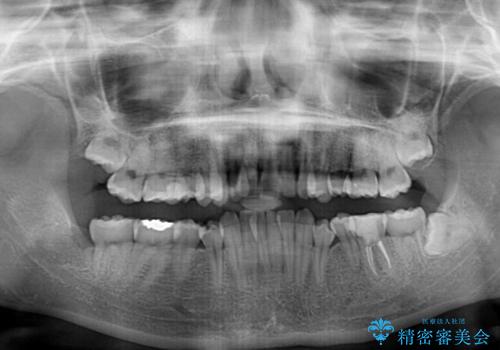

上下の前歯にデコボコがあり、更にはディープバイトにより下顎前歯の大半が隠れている状態でした。

上顎左右第一小臼歯の2本を抜歯し、ワイヤー装置を使用して咬み合わせ高さを改善しながら、歯列を整えて行くこととしました。

事前にむし歯の疑いがある歯があり、処置を行いましたが、矯正治療中に失活してしまい、ワイヤー装置除去後に、根管治療とセラミッククラウンによる補綴治療を行いました。